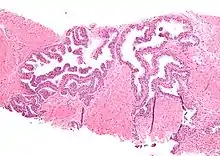

Micrograph showing high-grade prostatic intraepithelial neoplasia. H&E stain. | |

High-grade prostatic intraepithelial neoplasia (HGPIN) is an abnormality of prostatic glands and believed to precede the development of prostate adenocarcinoma (the most common form of prostate cancer).[1][2]

It may be referred to simply as prostatic intraepithelial neoplasia (PIN). It is considered to be a pre-malignancy, or carcinoma in situ, of the prostatic glands.

Histology

HGPIN typically has one of four different histologic patterns:[2]

- tufted (fascicular patterning)

- micropapillary,

- cribriform and,

- flat.

Its cytologic features are that of prostatic adenocarcinoma:

- presence of nucleoli,

- increased nuclear-to-cytoplasmic ratio and,

- increased nuclear size.

Microscopically, PIN is a collection of irregular, atypical epithelial cells. The architecture of the glands and ducts remains normal. The epithelial cells proliferate and crowding results in a pseudo-multilayer appearance. They remain fully contained within a prostate acinus (the berry-shaped termination of a gland, where the secretion is produced) or duct. The latter can be demonstrated with special staining techniques (immunohistochemistry for cytokeratins) to identify the basal cells forming the supporting layer of the acinus. In prostate cancer, the abnormal cells spread beyond the boundaries of the acinus and form clusters without basal cells. In HGPIN, the basal cell layer is disrupted but present. PIN is primarily found in the peripheral zone of the prostate (75-80%), rarely in the transition zone (10-15%) and very rarely in the central zone (5%), a distribution that parallels the zonal distribution for prostate carcinoma.[7]

Several architectural variants of PIN have been described, and many cases have multiple patterns. The main ones are tufting, micropapillary, cribriform, and flat. Although these different appearances may cause confusion with other conditions, they have not been found to be of clinical importance. Rarer types are signet-ring-cell, small-cell-neuroendocrine, mucinous, foamy, inverted, and with squamous differentiation.[3]